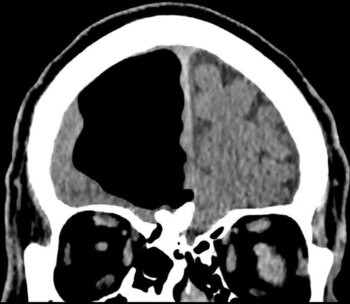

La sorpresa llevó luego de realizarle una tomografía y una resonancia magnética. No podían creerlo: prácticamente todo el lóbulo frontal derecho de este sujeto estaba desaparecido. Solo veían un espacio en blanco (o en negro).

Según determinaron, el paciente sufría de neumocefalia, la presencia de aire en el cráneo, una condición que suele presentarse en casos de cirugía al cerebro, infecciones o heridas faciales, aunque con burbujas o espacios de aire mucho más pequeños.

En este caso, la cavidad llegaba a medir casi nueve centímetros de largo en su parte más grande, algo difícil de encontrar en los libros de historia médica.

La causa más probable, según el equipo de investigadores, fue un tumor benigno formado en los senos paranasales del paciente, que erosionaron la base del cráneo y permitieron la formación de la cavidad.